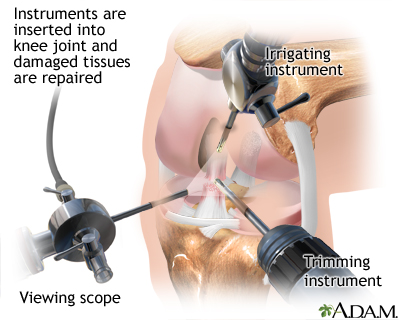

If there is damage to the bone and cartilage, or if the kneecap continues to be unstable, you may need surgery to stabilize the kneecap. This may be done using arthroscopic or open surgery.